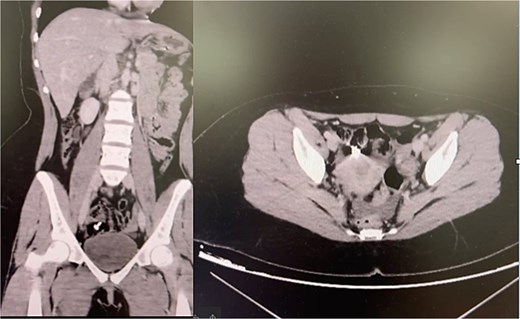

A 22-year-old woman with suspected mood dysregulation ingested a 4-cm nail. Abdominal radiographs revealed a metallic foreign body in the right lower quadrant; CT confirmed its location in the cecum (Fig. 3). She remained asymptomatic and was managed conservatively with a high-fiber diet and serial abdominal imaging. The nail passed uneventfully within 72 h.

Teaching point: Not all sharp objects mandate immediate surgery. Small, linear metallic items may pass spontaneously under close monitoring, but vigilance is essential to detect perforation or obstruction [7–9].